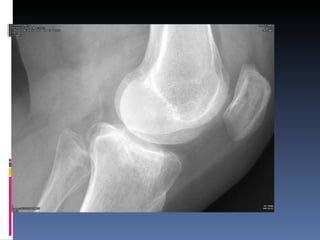

Fractura Intra-articular  involucra la superficie articular de la articulacion subyacente